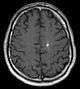

Diagnosis is generally made by magnetic resonance imaging (MRI), particularly using a specific imaging technique known as a gradient-echo sequence MRI, which can unmask small or punctate lesions that may otherwise remain undetected. These lesions are also more conspicuous on FLAIR imaging compared to standard T2 weighing. FLAIR imaging is different from gradient sequences. Rather, it is similar to T2 weighing but suppresses free-flowing fluid signal. Sometimes quiescent CCMs can be revealed as incidental findings during MRI exams ordered for other reasons. Many cavernous hemangiomas are detected "accidentally" during MRIs searching for other pathologies. These "incidentalomas" are generally asymptomatic. In the case of hemorrhage, however, a CT scan is more efficient at showing new blood than an MRI, and when brain hemorrhage is suspected, a CT scan may be ordered first, followed by an MRI to confirm the type of lesion that has bled.

Sometimes the lesion appearance imaged by MRI remains inconclusive. Consequently neurosurgeons will order a cerebral angiogram or magnetic resonance angiogram (MRA). Since CCMs are low flow lesions (they are hooked into the venous side of the circulatory system), they will be angiographically occult (invisible). If a lesion is discernible via angiogram in the same location as in the MRI, then an arteriovenous malformation (AVM) becomes the primary concern.